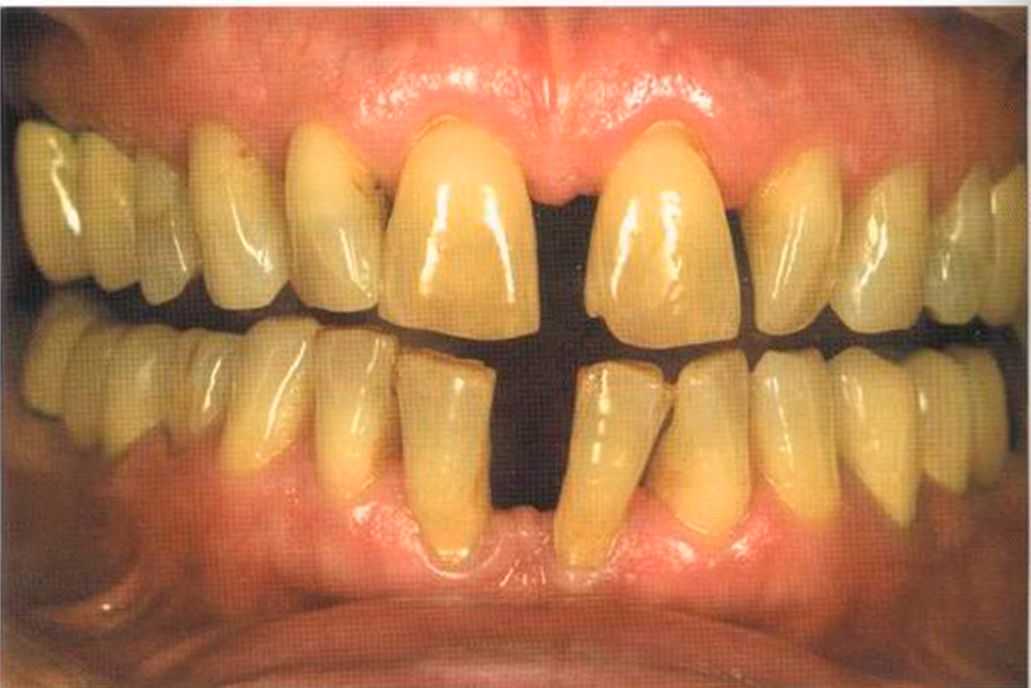

Эта женщина пришла в клинику доктора Лангханке с металлокерамической реставрацией.

Ей не нравились типичные в таких случаях темные края коронок и опаковость керамики.

Цвет 1М1 до 1М2 основной цвет в данном случае.

Отмечаем, что десна здоровая. Она гармонирует с коронкой ln-Сегат за счет отличных свойств материала

и отличного краевого прилегания.

Теперь коронки в области боковой группы зубов не нравятся, и в скором времени их тоже будем переделывать.

Коронки выполнялись в моей лаборатории вместе с пациентом. Мы работали долгих четыре часа, чтобы всем понравился результат. Обратите внимание на отражение света по краевым валикам. Мезиальные валики коронки 12 зуба гармонично переходят в дистальные валики 42 зуба. В идеальном варианте «отражающиеся валики» должны проходить по прямой линии. Это привило для всех мезиальных и дистальных валиков фронтальной группы зубов. Оно имеет очень важное значение и влияет на результат нашей работы.

Эти валики проходят перемещаясь, однако по одной линии. Примером здесь являются мезиальные поверхности на коронке 11 и на 31.